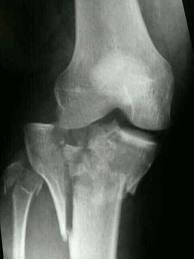

СУГЛОБ СКЛАДНИЙ. СУГЛОБОВА КАПСУЛА ТОНКА, УТВОРЮЄ БАГАТО СУМОК, ЯКІ СПОЛУЧАЮТЬСЯ ІЗ СУГЛОБОВОЮ ПОРОЖНИНОЮ. ЦЕ СПРИЯЄ ПЕРЕХОДУ ЗАПАЛЬНИХ ПРОЦЕСІВ (Є ДІАГНОЗ: БУРСИТ). ДЕ ВИ БАЧИТЕ ЦЕЙ СУГЛОБ.

варіанти відповідей

Запитання 59

СУГЛОБ СКЛАДНИЙ. УТВОРЕНИЙ СУГЛОБОВИМИ ПОВЕРХНЯМИ МЕДІАЛЬНОГО І ЛАТЕРАЛЬНОГО ВИРОСТКІВ, ЯКІ Є В ОБОХ КІСТКАХ, ЩО ЙОГО УТВОРЮЮТЬ. РОЗПІЗНАЙТЕ СУГЛОБ.

КОЛІННИЙ С.

ЛІКТЬОВИЙ С.

ГОМІЛКОВО--СТОПНИЙ С.

ПРОМЕНЕВО-ЗАП'ЯСТКОВИЙ С.

Запитання 51

РОЗПІЗНАЙТЕ СУГЛОБ, ЯКИЙ ЗАБЕЗПЕЧУЄ РУХИ ГОМІЛКИ.

РОЗПІЗНАЙТЕ СКЛАДНИЙ СУГЛОБ, ЯКИЙ СКЛАДАЄТЬСЯ З ТРЬОХ КІСТОК, ОДНА З ЯКИХ РОЗТАШОВАНА В СУХОЖИЛКУ ЧОТИРИГОЛОВОГО М'ЯЗА СТЕГНА.